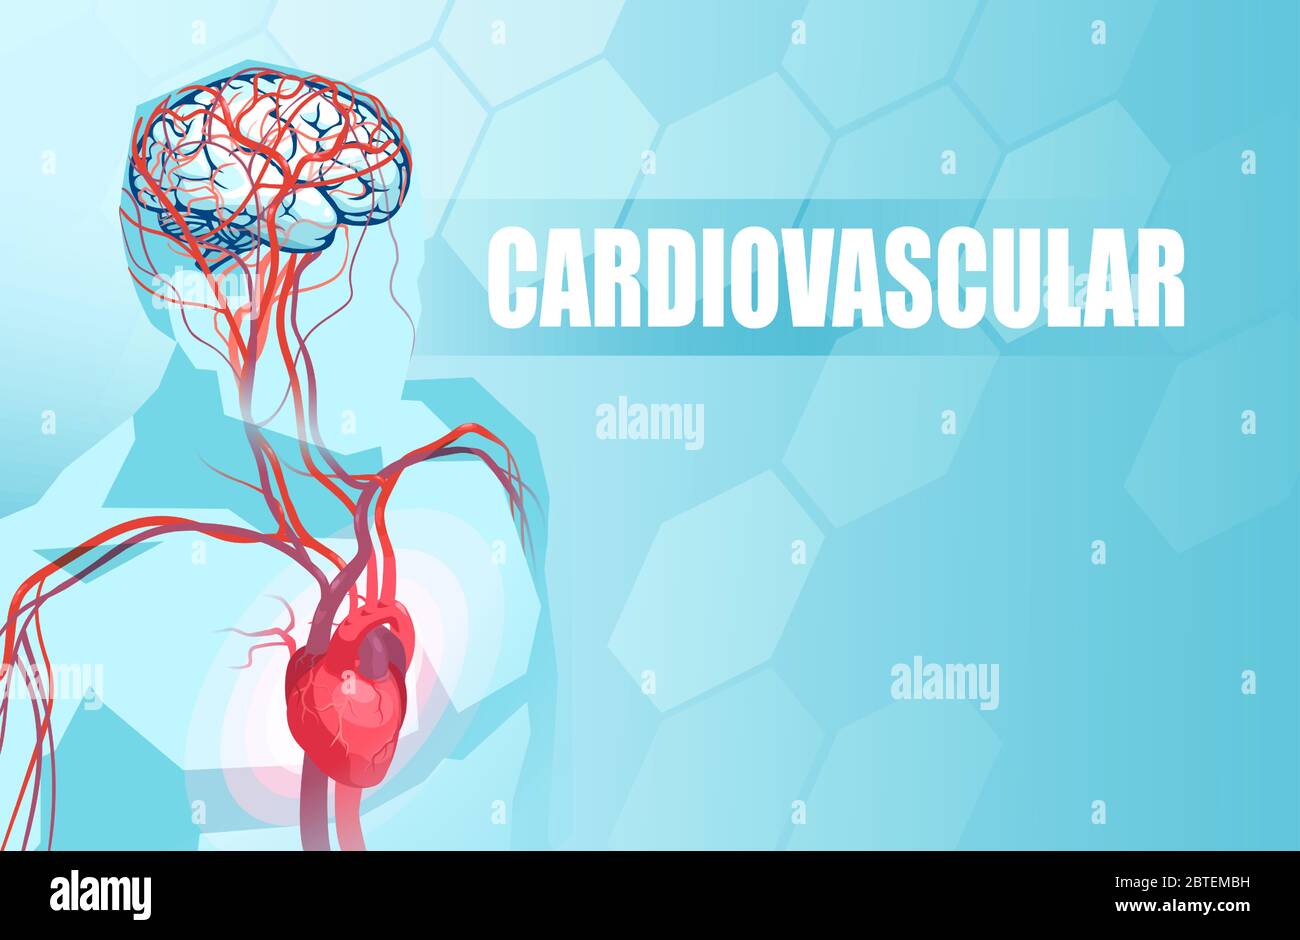

RF2BTEMBH–Schematische Darstellung des menschlichen Kreislaufsystems, der Herzanatomie und der Gehirnblutversorgung